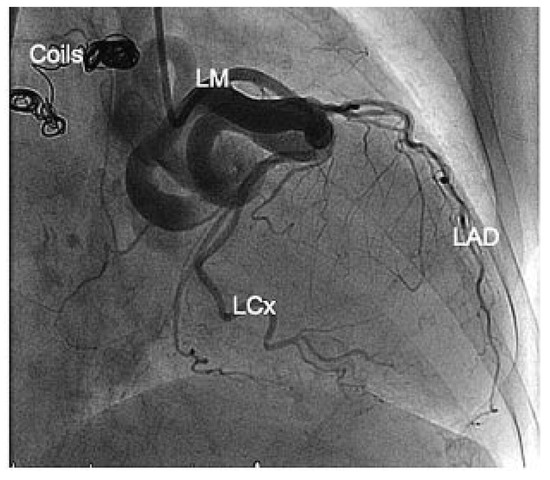

Platinum Reward for Theft, or the Percutaneous Treatment of Coronary Steal Due to a Giant Coronary Artery Fistula

An 89-year-old sister who presented with angina pectoris and signs of acute left ventricular failure had a history of chronic dyspnoea aggravated a few days prior to admission by orthopnoea and nycturia. [...] Full article